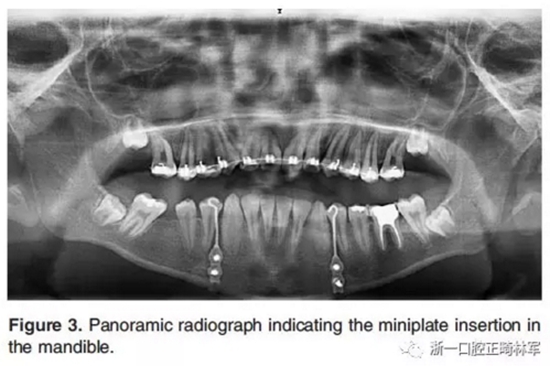

然后在全身麻醉下對所有患者進行手術(shù)。在手術(shù)的第一步,在下頜兩側(cè)尖牙和第一前磨牙之間放置鈦板,并固定一個牽引鉤,位于尖牙和第一前磨牙的鄰間隙(Figure 2a,F(xiàn)igure 3)。手術(shù)的第二步,進行不完全的Le Fort I截骨術(shù)以釋放上頜骨(Figure 2b)。Le Fort I截骨術(shù)中包括上頜骨的鼻腔外側(cè)壁,但鼻壁和鼻中隔保持完整,不包括翼板。